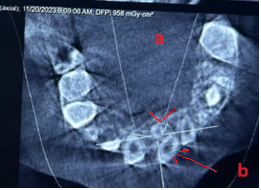

Khám lâm sàng thấy chậm mọc răng so với tuổi mọc dự kiến. Chẳng hạn như tuổi dự kiến mọc răng cửa giữa hàm trên vào khoảng 7-8 tuổi. Khi đến độ tuổi này nếu cả hai răng chưa mọc hoặc đã mọc một răng trong khi răng đối xứng chưa mọc hoặc mọc chậm thì nghi ngờ khả năng có răng thừa ngầm gây cản trở sự mọc răng. Hoặc phát hiện khe răng thưa răng cửa hàm trên hoặc có bất kì sự mọc lệch lạc nào của răng cửa hàm trên đều cũng nên chụp XQ kiểm tra sự hiện diện của răng thừa. Việc chẩn đoán bằng XQ là rất quan trọng. Tại BV Đa khoa Tỉnh Quảng Trị có đầy đủ các phương tiện chẩn đoán như XQ cận chóp, XQ răng toàn cảnh và đặc biệt là phương tiện chụp cắt lớp vi tính chùm tia hình nón (CT Cone Beam) có thể phát hiện răng thừa theo 3 chiều không gian mà các phương tiện khác có thể không phát hiện ra. Minh họa trường hợp cháu trai 8 tuổi sau đây là một ví dụ.

Răng thừa (b) mọc trong vòm miệng khiến cho R22 (a) mọc lệch xoay trục XQ răng toàn cảnh không thấy răng thừa do R21 (a) che khuất,(b) là R22 bị xoay trục

Hình ảnh răng thừa (a) xuất hiện rất rõ trên CT Cone Beam, (b) là hình ảnh R21

Hình 3: Tính ưu việt của CT Cone Beam trong chẩn đoán răng thừa

(Nguồn: Bệnh viện Đa khoa Tỉnh Quảng Trị)